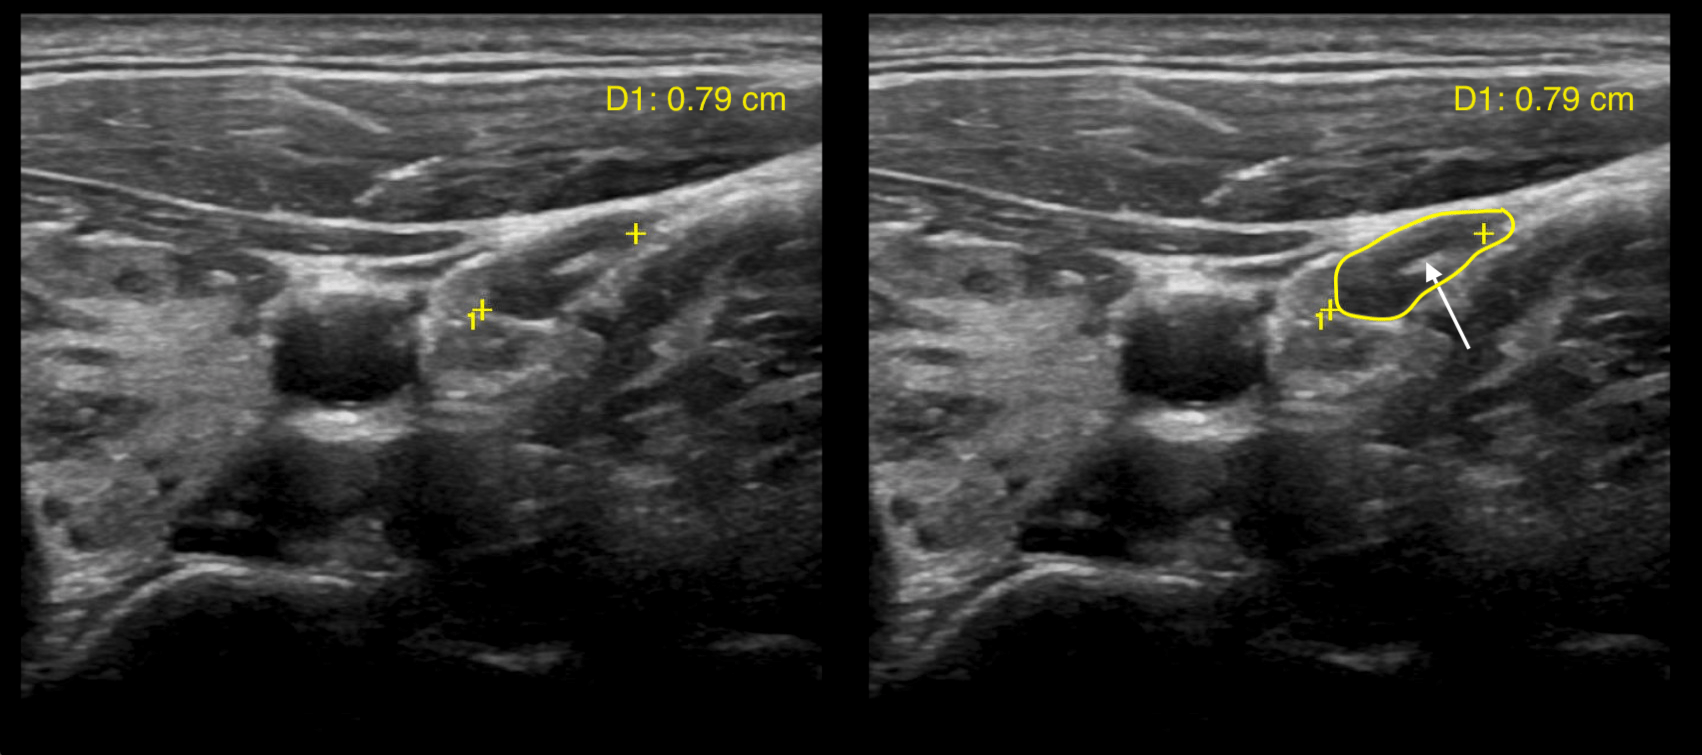

Condition Specific Radiology Hashimoto Thyroiditis Stepwards Swiss Cheese Appearance Ultrasound the thorough examination of vaginal sonographic image can reveal space between normal appearing endometrium and swiss. ultrasound (us) is the accepted primary modality for the evaluation of abnormal uterine bleeding. Multiple vascular lacunae (spaces) within the placenta (‘swiss cheese’ appearance) with turbulent flow (peak systolic velocity >15. endometrial hyperplasia can also be observed using ultrasonography, which is. Swiss Cheese Appearance Ultrasound.

Condition Specific Radiology Hashimoto Thyroiditis Stepwards Swiss Cheese Appearance Ultrasound sonographic findings of thick uterine endometrium with swiss cheese appearance need to be considered. Multiple vascular lacunae (spaces) within the placenta (‘swiss cheese’ appearance) with turbulent flow (peak systolic velocity >15. the transvaginal sonographic image of paec before (d) and after (e). the thorough examination of vaginal sonographic image can reveal space between normal appearing endometrium and. Swiss Cheese Appearance Ultrasound.